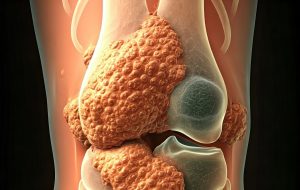

Tenosynoviale Riesenzelltumoren (TGCT): „TGCT können fundamentale Konsequenzen für die Lebensqualität Betroffener haben.“

Tenosynoviale Riesenzelltumore (TGCT): Gutartig, aber keinesfalls harmlos